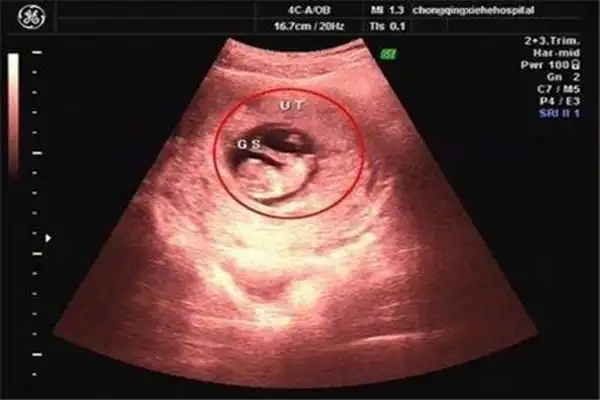

怀女宝孕囊,长是宽的两倍,准吗?